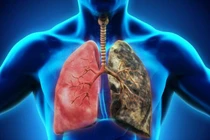

Phổi đảm nhận nhiệm vụ hô hấp và cung cấp khí oxy cho hồng cầu, đảm bảo duy trì sự sống của con người. Tuy nhiên, nhiều thói quen hàng ngày mà chúng ta thường không để ý đến có thể gây hại cho sức khỏe của phổi.

Trong nỗ lực ngừa ung thư phổi, từ bỏ thói quen hút thuốc lá là một trong những yếu tố không thể thiếu. Ngoài ra, bạn có thể tăng khả năng ngăn ngừa ung thư phổi bằng việc thường xuyên ăn những thực phẩm dưới đây.